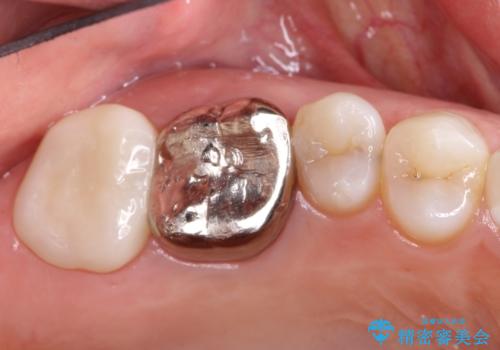

根っこの感染 再治療をしてかぶせ物を製作する

- 古いかぶせ物・土台・根管充填材をすべて除去し、内部を徹底的に洗浄する

→改めて土台を築造し、かぶせ物を新製する